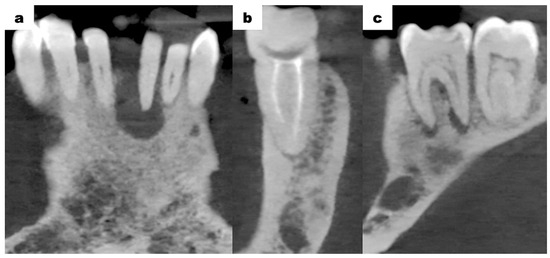

Cone-beam computed tomography (CBCT—cone-beam computed tomography) scans of the mandible, which were provided by the patient, revealed bone resorption around tooth 31. The lateral surfaces of the apices of teeth 41 and 32 were adjacent to the periapical lesion of tooth 31 (Figure 3a). Tooth 46 was treated endodontically for a deficiency of filling material in the apical region of the roots (Figure 3b). Tooth 47 showed a carious lesion. Tooth 36 exhibited extensive periapical changes (Figure 3c). Tooth 38 was partially retained in the horizontal, mesial-angular position with no eruption potential. No inflammatory cysts were found around the crown of the retained tooth. There were no signs of resorption of tooth 37 (Figure 4a). However, the distal root surface of tooth 37 was exposed due to the adjacent position of tooth 38, enabling plaque retention. This might be a potential source of inflammation (Figure 4b). In the event of peri-coronal inflammation, tooth 38 will be eligible for an extraction in the hospital setting. CBCT scans revealed areas of bone thinning in the chin region, potentially due to irradiation treatment when the patient was at the developmental age (Figure 4c).

Figure 3. CBCT examination scans before initiation of treatment; (a) tooth 31—inflammatory change involving the entire root; (b) tooth 46—no trace of filling material in the root canals in the apical region, a suspected periapical lesion; (c) tooth 36—periapical inflammatory changes visible around both roots.